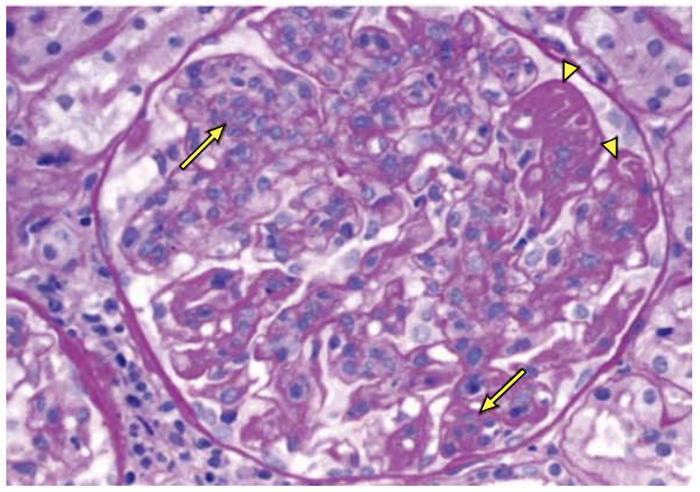

Mulher de 18 anos, com diagnóstico de lúpus eritematoso sistêmico (LES), realizou biópsia renal.

Microscopia ótica: 24 glomérulos, 18 dos quais comprometidos conforme imagem a seguir:

(Arquivo pessoal; imagem usada com autorização)

A classificação da nefrite lúpica é: